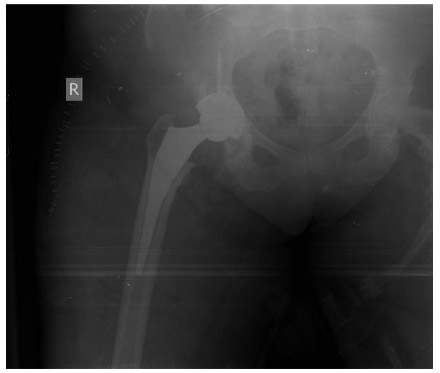

Post-surgery: The X-ray shows a complete uncemented hip replacement on the right side.